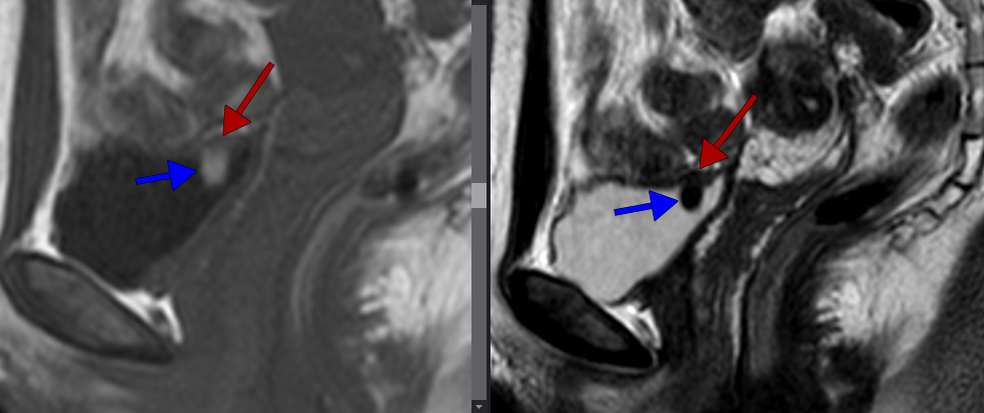

Наружный эндометриоз мочевого пузыря на сагиттальных Т1-ВИ и Т2-ВИ: определяется низкоинтенсивное утолщение стенки мочевого пузыря (красные стрелки) и наличие пролабирующего в просвет мочевого пузыря образования с геморрагическим содержимым: гиперинтенсивным на Т1 и гипоинтенсивным на Т2 (синии стрелки).